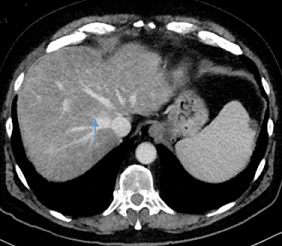

At the age of 66 the patient was diagnosed with a 4 cm pancreas tail tumor with synchronous liver metastasis in Positron-Emissions-Tomographie/Computer Tomographie (PET/CT) in 2014 (Figure 1A&1B). Initial CA 19-9 was 181 kU/l (Figure 2) in June 2014. The patient was oligosymptomatic, he had spine pain, fatigue and no significant weight loss. At the age of 65, he had some kind of belly pain and received a CT of the abdomen in 2013, however his pancreas and other organs were clean. In retrospective the cancer was already seen on that CT without liver metastasis (Figure 3). His risk factor for pancreas carcinoma were smoking, regular alcohol consumption and a positive family history for cancer. He was a smoker (30 pack-years (PY)) and quit in 1982. Despite the presence of liver metastasis the patient wished to be operated on. Preoperative the patient received pseudo-neoadjuvant chemotherapy mFOLFIRINOX (15 cycles) from May 2014 until January 2015.  After chemotherapy a regression of the tumor, liver metastasis (Figure 4) and CA 19-9 (Figure 2) was observed. However a new 19 mm metastasis of liver occurred. Despite that fact a successful pancreas tail resection with lymphadenectomy and splenectomy was performed on in April 2015. Based on the histopatology the tumor staging was pT3, G3, L0, V1, Pn1, R0. The morphology of the tumor was poorly differentiated adenosquamous carcinoma and tumor size was 2.5 cm diameter. Radiofrequency Ablation (RFA) of liver metastasis were done in April 2015. One year postoperatively diabetes mellitus type 2 was diagnosed and insulin therapy was started in March 2015.

Figure 3: Axial image from a contrast-enchanced CT scan of the abdomen in our patient with 4cm pancreas tail cancer showing a very early stage.